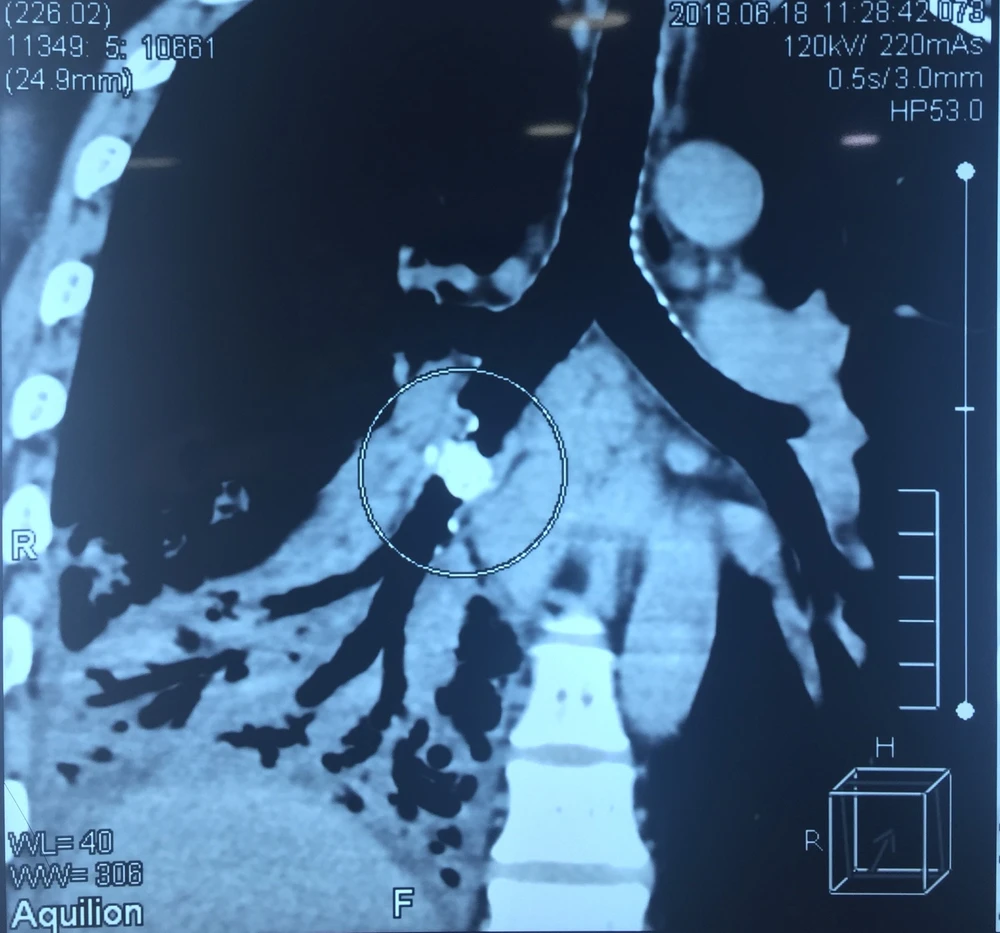

Bệnh nhân là ông NHT (41 tuổi) bị ho khạc đàm vàng, sốt cao liên tục ba ngày, cơ thể mệt mỏi và được chẩn đoán viêm phổi thùy dưới bên phải. Nguyên nhân do dị vật là mảnh xương cá nằm trong phế quản của thùy dưới phổi phải.

Dị vật xương cá nằm trong phổi bệnh nhân. Ảnh: BVCC

Do mảnh xương cá nằm trong cơ thể quá lâu nên đã ghim sâu vào trong phần phế quản trung gian khiến phổi bị đông đặc và viêm mủ mạn tính, không thể nội soi gắp thông thường. Vì vậy các bác sĩ đã quyết định mổ hở, lấy dị vật ra ngoài, cắt phần phổi bị tổn thương. Đến ngày 29-6 vừa qua, tình trạng sức khỏe người bệnh hồi phục tốt, bác sĩ điều trị đã cho xuất viện.